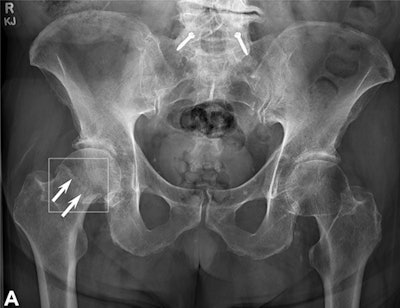

The dataset included at least 60 examinations for each of the following anatomic regions: foot and ankle, knee and leg, hip and pelvis, hand and wrist, elbow and arm, shoulder and clavicle, rib cage, and thoracolumbar spine. When the AI model's "confidence level" for identifying fractures was surpassed, it highlighted regions of interest with a white square box on the radiograph.